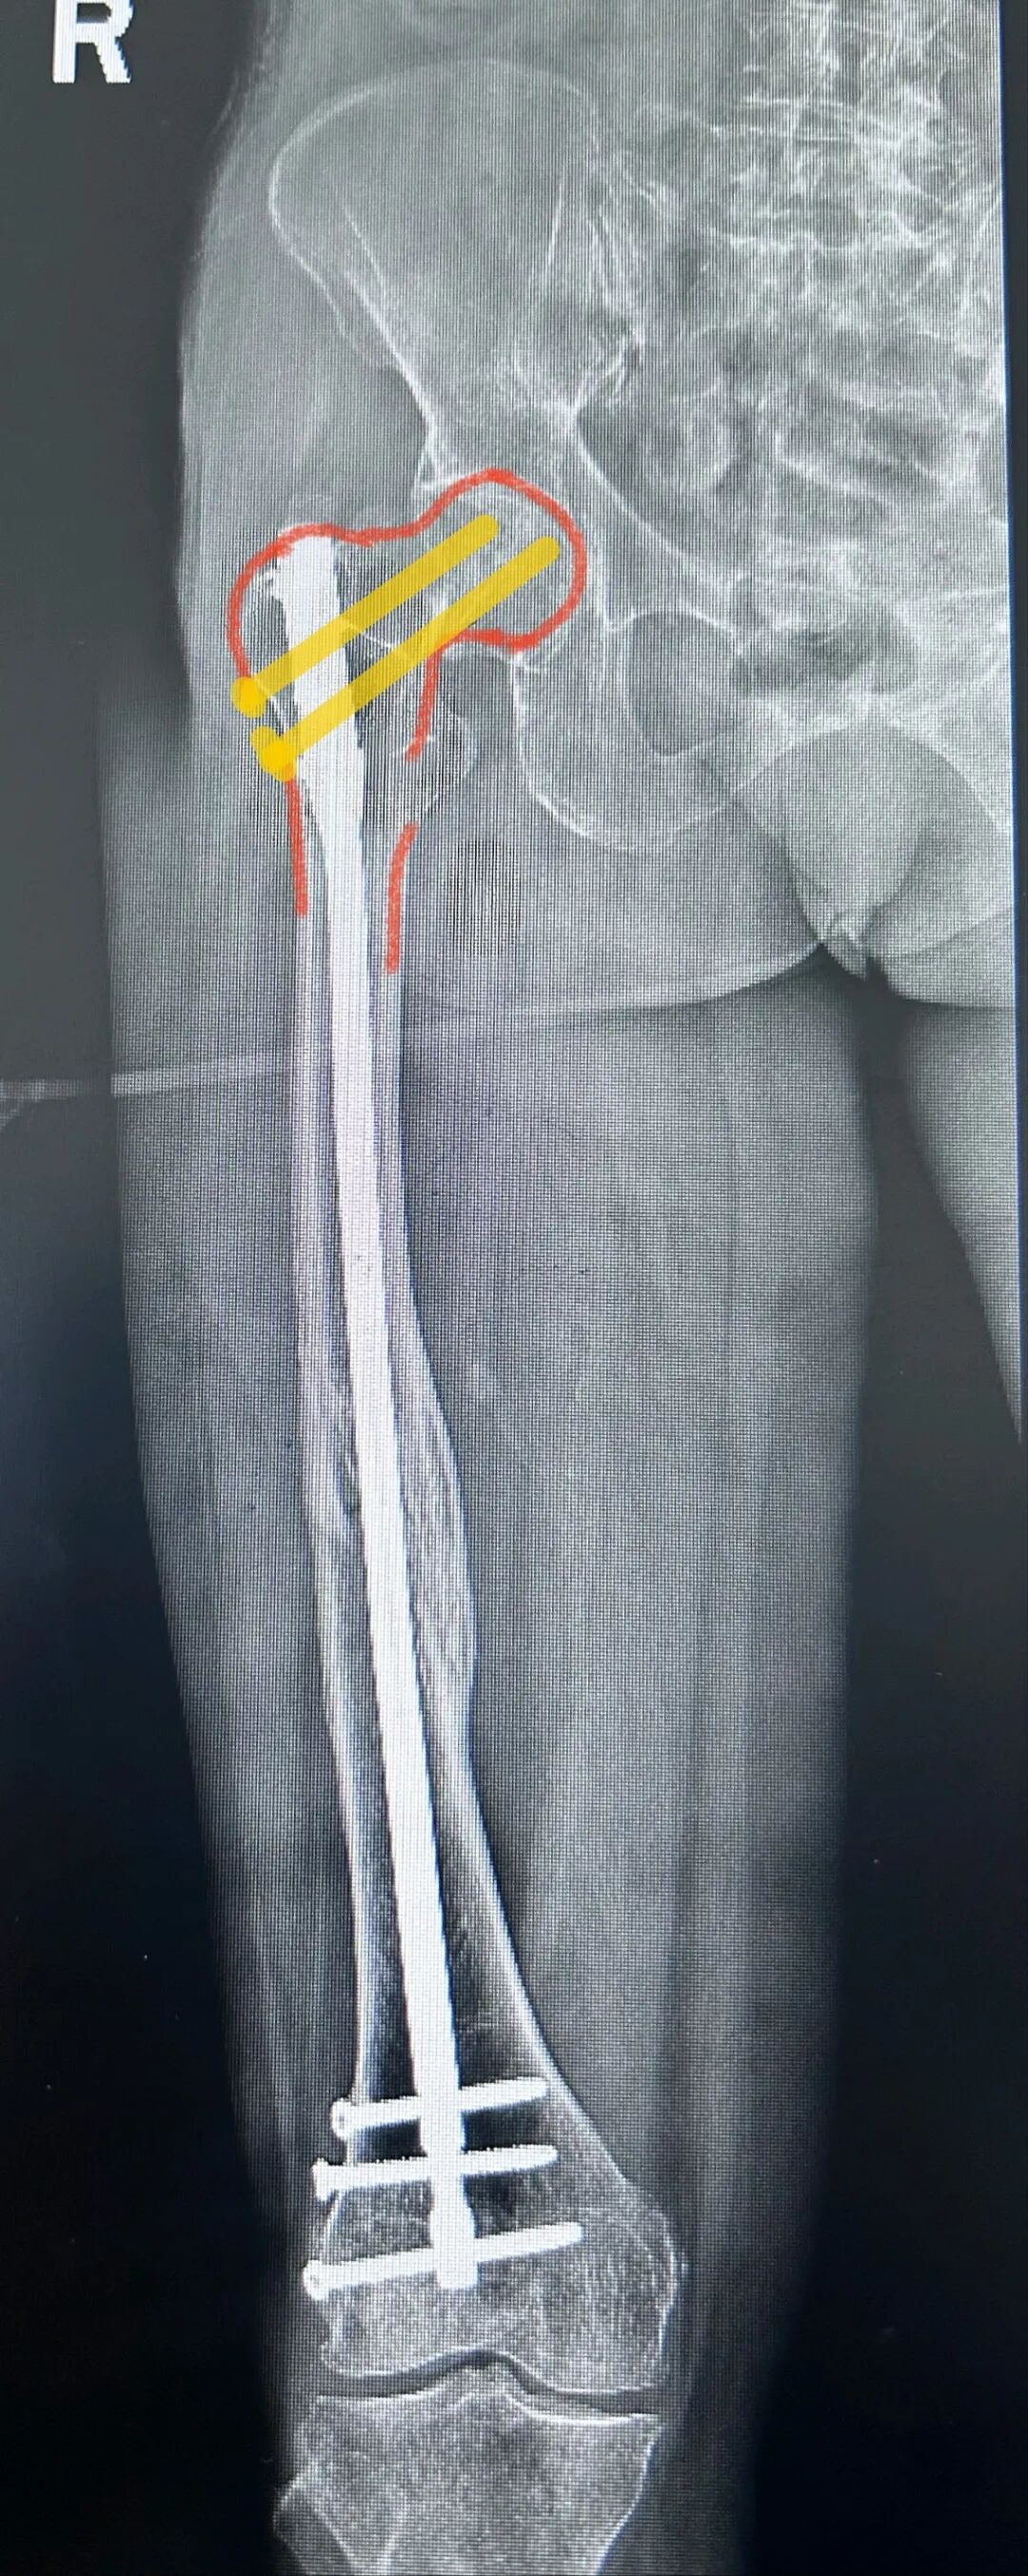

我们给予翻修

1,顺行髓内钉,头颈模式

2,全长保护,

3,最粗,够长

4,扩髓约等于植骨

术后5个月完全愈合

这样全长保护

转子下,股骨颈或者股骨远端再骨折的概率

是不是非常小

几乎不会再出现?

这个患者术后14个月取了髓内钉

术后已经随访了两年